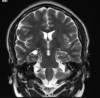

Q

A

Esclerose mesial temporal

Observe a perda de volume, que indica atrofia e causa aumento secundário do corno temporal do ventrículo lateral.

O sinal alto no hipocampo reflete a gliose.